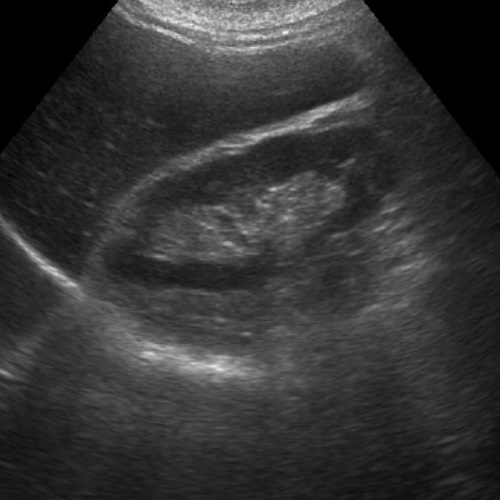

La diagnosi ecografica della diastasi dei retti addominali è uno dei metodi più accurati e non invasivi per valutare l'entità della separazione tra i muscoli retti addominali e monitorarne l'evoluzione. Durante l'esame, l'ecografo permette di visualizzare i muscoli addominali e la linea alba, misurando la distanza tra i muscoli retti nella posizione di riposo e durante contrazioni leggere, come ad esempio un sollevamento della testa o delle spalle.

1. Ampiezza della separazione: si misura lo spazio tra i muscoli retti, generalmente a livello della regione sopra e sotto l'ombelico. Una distanza superiore a 2-2,5 cm è spesso indicativa di diastasi.

2. Integrità della linea alba: si valuta il grado di assottigliamento o cedimento del tessuto connettivo, che influisce sulla capacità di supporto dell'addome.

3. Coinvolgimento delle strutture circostanti: l’ecografia può rilevare eventuali ernie o alterazioni della struttura muscolare e connettiva che potrebbero richiedere un trattamento specifico.